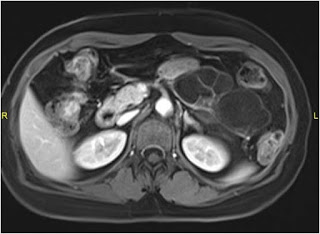

Figure B: Contrast enhanced abdominal magnetic resonance imaging scan

In our patient, the contrast enhanced abdominal computed tomography scan shows a lobulated cystic neoplasm with septations in the body and tail of pancreas with thin (< 2 mm) non enhancing walls. The cystic spaces (6 in number) are > 2 cm (Figure A). These findings are better appreciated in contrast enhanced abdominal magnetic resonance imaging scan (Figure B). At magnetic resonance cholangio-pancreatography (MRCP), the main pancreatic duct (MPD) is not dilated in its entire course and there was no duct – cyst communication (Figure C). Hence a diagnosis of SOA was made.3

Branch chain IPMN was ruled out as the MPD was of normal caliber at MRCP and the cystic tumor did not have communication with the main pancreatic duct (Figure B).